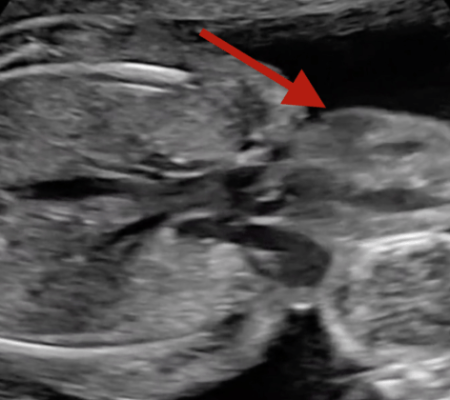

No caso de Vanellope Hope Wilkins, sua condição foi revelada no ultrassom de 16 semanas. Por esse motivo, a menina nasceu por meio de um parto cesárea. Na ocasião, além de precisar de uma série de cirurgias para corrigir sua condição, ela tinha menos de 10% de chance de sobreviver.